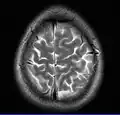

- T2-weighted (T2W) images: CSF is light, but fat (and thus white matter) is darker than with T1. T2-weighted images are useful for visualizing pathology.[26]

Normal axial T2-weighted MR image of the brain -